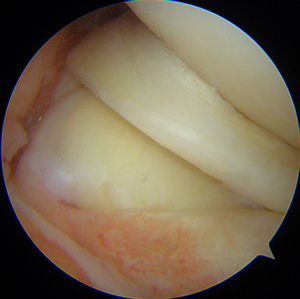

Sous arthroscopie, image d'une fissure dégénérative du ménisque qui est "feuilleté". Notez que parallèlement, le cartilage est parfait, comme neuf.